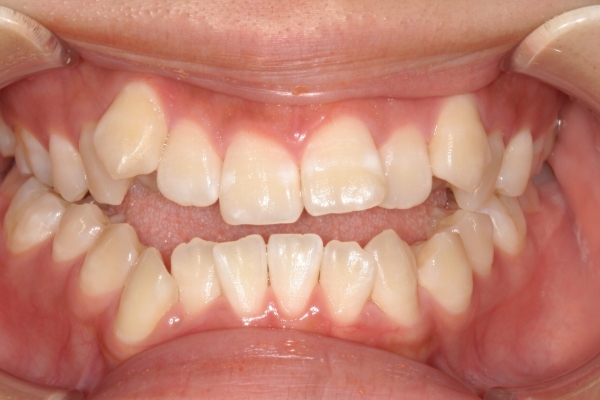

BEFORE

治療前

PROCESS

3か月

AFTER

治療後

骨格的に下あごが前下方に長いことが原因で、受け口、開咬(前歯が当たらない)の症状がでていました。また下あごが右にずれており、その影響で上下の歯列正中(真ん中)の大きなずれも生じていました。顎変形症手術も選択肢の一つでしたが、患者さまの希望もあり、下顎左側小臼歯の抜歯をして通常の歯列矯正で治療をしました。

治療後は、前歯、奥歯の噛み合わせが整い、上下の歯列の真ん中が一致しました。歯列全体のアーチも安定し、機能面・審美面のどちらも大きく改善されました。